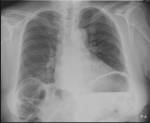

| C | Cardiac | • should be <50% of the chest diameter on PA films and <60% on AP films. • Check for the heart shape, calcifications, and prosthetic valves. |

| G | Great vessels Gastric bubble | • aortic knuckle size and shape • gastric bubble not displaced? |